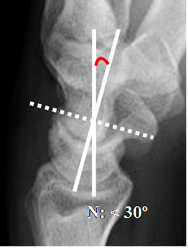

Hay 2 ángulos muy importantes en el estudio de la inestabilidad. Los ángulos escafolunado y grandelunado, que son medidos en Rx lateral.

El ángulo escafolunado tiene una amplitud normal entre 30º y 60º. (4).

El eje del escafoides se traza uniendo los bordes anteriores superior e inferior. El del lunado, por una línea perpendicular a la unión de sus polos distales. (Fig 19).

El ángulo grandelunado tiene una amplitud normal entre 0º y 30º. (4).

El eje del hueso grande se traza de la parte media de la cabeza, a la parte mas inferior de su superficie articular. (Fig 20).

Fig 19. Angulo escafolunado.

A: Rx lateral. Intersección entre los ejes de los huesos escafoides y lunado.

Fig 20. Angulo grandelunado.

A: Rx lateral. Intersección entre los ejes de los huesos grande y lunado.